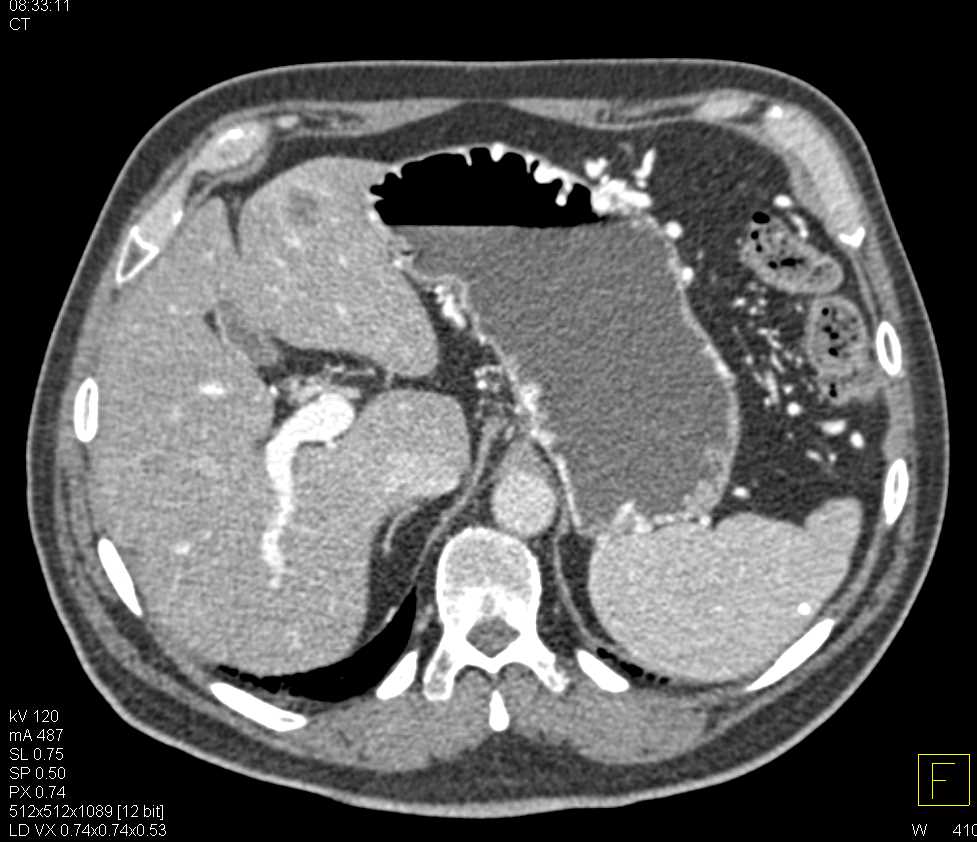

Gastric Adenocarcinoma